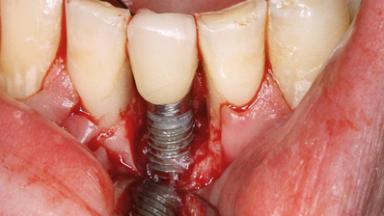

A 27-year-old male was referred to the periodontist for assessment and management of implant site 41. The implant had been placed nine years previously and restored with a screw-retained single crown. The patient was a cigarette smoker in good general health. He reported he had reduced his smoking habit from 25 cigarettes per day to 15 cigarettes per day in the previous six months. On examination, there was calculus and plaque present at the lower anterior teeth and at implant site 41. Localized attachment loss was observed at teeth 32 and 42, with 2–3 mm of gingival recession. At implant site 41, there were 8–9 mm probing depths with suppuration and bleeding on probing.